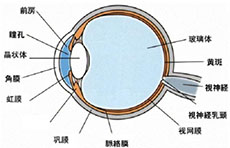

带状疱疹病毒性睑皮炎

疾病介绍:本病是由带状疱疹病毒感染三叉神经半月神经节或三叉神经第一支所致,多见于老年人或体弱者。多有发热、乏力、全身不适的前驱症状。随后病变区出现剧烈…【详细】

单纯疱疹病毒性角膜炎

疾病介绍:单纯疱疹病毒性角膜炎是由单纯疱疹病毒( HSV)引起的角膜感染,患者多为复发性感染病例。原发性单纯疱疹病毒感染常在幼儿阶段,多表现为急性滤泡性结…【详细】